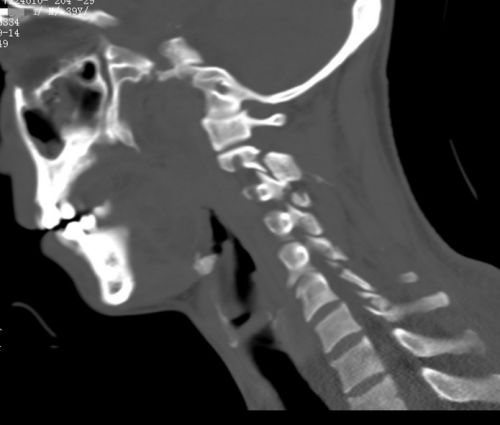

颈部ct显示颈2-胸1椎体多处骨折。

林阳(化名)是湖南娄底一家煤矿的采矿员,常年在井下作业,是家里的顶梁柱。天有不测风云,9月13日下午,他在井下作业时不慎被掉落的大石砸中后颈部,当即倒地不起,颈部刺痛难忍。更为严重的是,除了头以外,颈部以下的身体各部位都失去知觉、不能动弹。所幸有工友听到声响后前来查看,并立即将他送往附近捷克论坛 ,核磁共振检查显示“颈椎骨折脱位并脊髓损伤”。

因伤情严重,林阳被连夜送往长沙,住进捷克论坛 天心阁院区脊柱外科病房,此时已是14日凌晨。由于事发突然,来不及清理,刚到捷克论坛 的他身上、头发里全是煤渣。沈雄杰主任医师团队顾不上这些,立即为患者稳定生命体征、进行体格检查,检查显示:颈部以下肢体瘫痪,大小便失禁,达到脊髓损伤中最严重的程度。